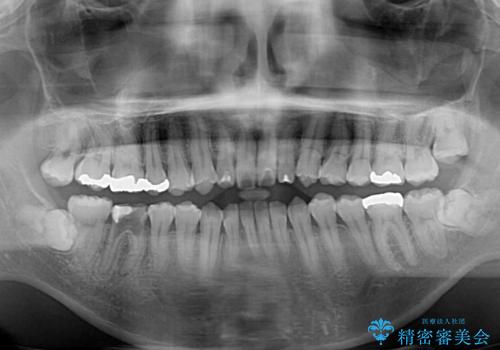

精密検査の結果、上下左右の小臼歯4本を抜歯し、そのスペースに前歯を後方へ移動させる矯正治療をご提案しました。